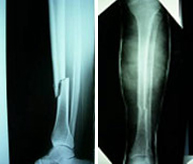

La región de la piernaengloba las diáfisis o zonas centrales de la tibia y el peroné. Son las fracturas de huesos largos (fémur, tibia, húmero, cúbito y radio) más frecuentes en el adulto y pueden producirse por un impacto directo (accidentes de tráfico, caídas desde gran altura, deportes de contacto o de motor) o por un mecanismo indirecto (torsión de la pierna en deportes de salto o sobrecarga repetida en bailarines y reclutas). El tratamiento varía en función del desplazamiento y el grado de afectación de la musculatura y piel circundante. El avance en las técnicas quirúrgicas ha permitido, cuando la indicación lo requiere, el empleo de una cirugía mínimamente invasiva querepara grandes fracturas a través de mínimas heridas disminuyendo la agresión al tejido y favoreciendo la rápida incorporación a la actividad diaria.